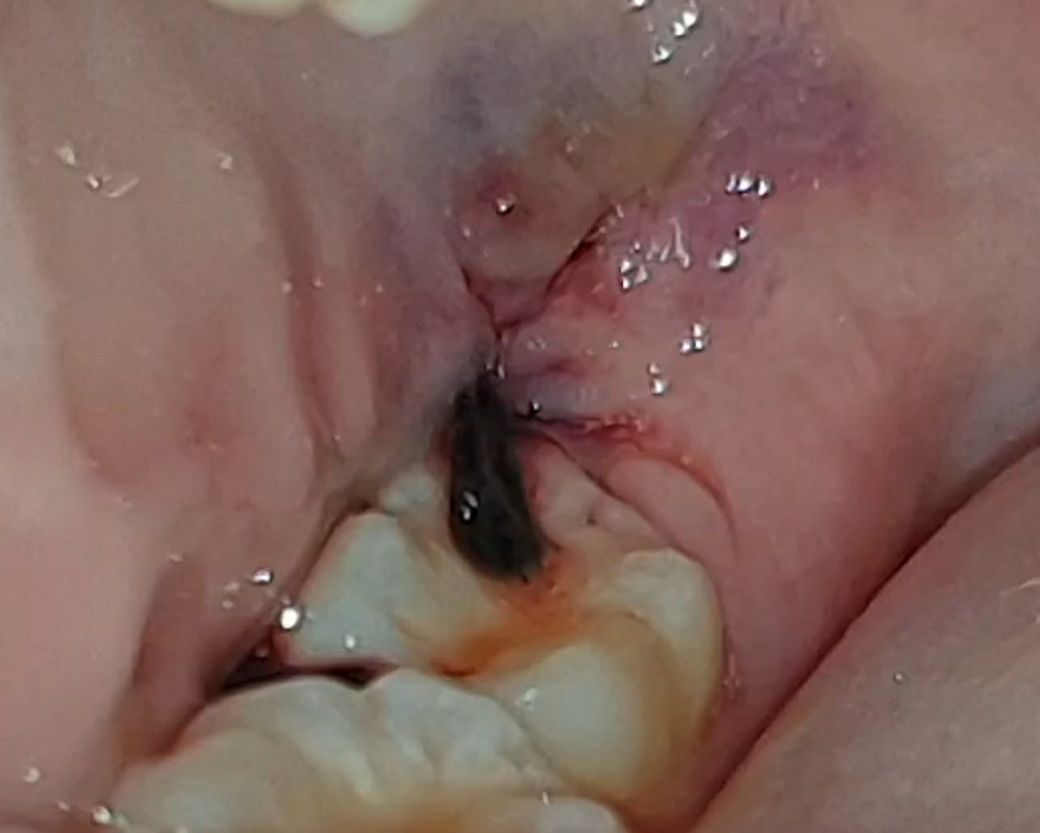

매복 사랑니 발치 후 실밥이 풀린 것 같아요

그저께 발치하고 어제 오후에 실밥이 풀렸는지 피가 조금씩 스며 나왔어요 자고 일어나니까 오늘은 저런 상태인데 양치했을 때만 피가 조금 나오다 말아요 어금니에 걸쳐져 있는게 실밥인데 치과는 담주 실밥 푸는 날에 가도 되나요?

• 1번 째 사진

실밥이 풀리더라도 문제가 생기는 경우는 거의 없습니다. 지혈이 잘되었다면 내원날짜에 가시면 됩니다.

피가 많이 나시는거 같은데 최대한 사랑니 발치한곳에 자극을 주지 않는게 좋습니다. 실밥은 약속된 시간에 가셔서 푸셔도 될것같습니다.

실밥이 좀 길게 남겨지긴 했으나

정상이십니다.

걱정하지 않으셔도 됩니다.